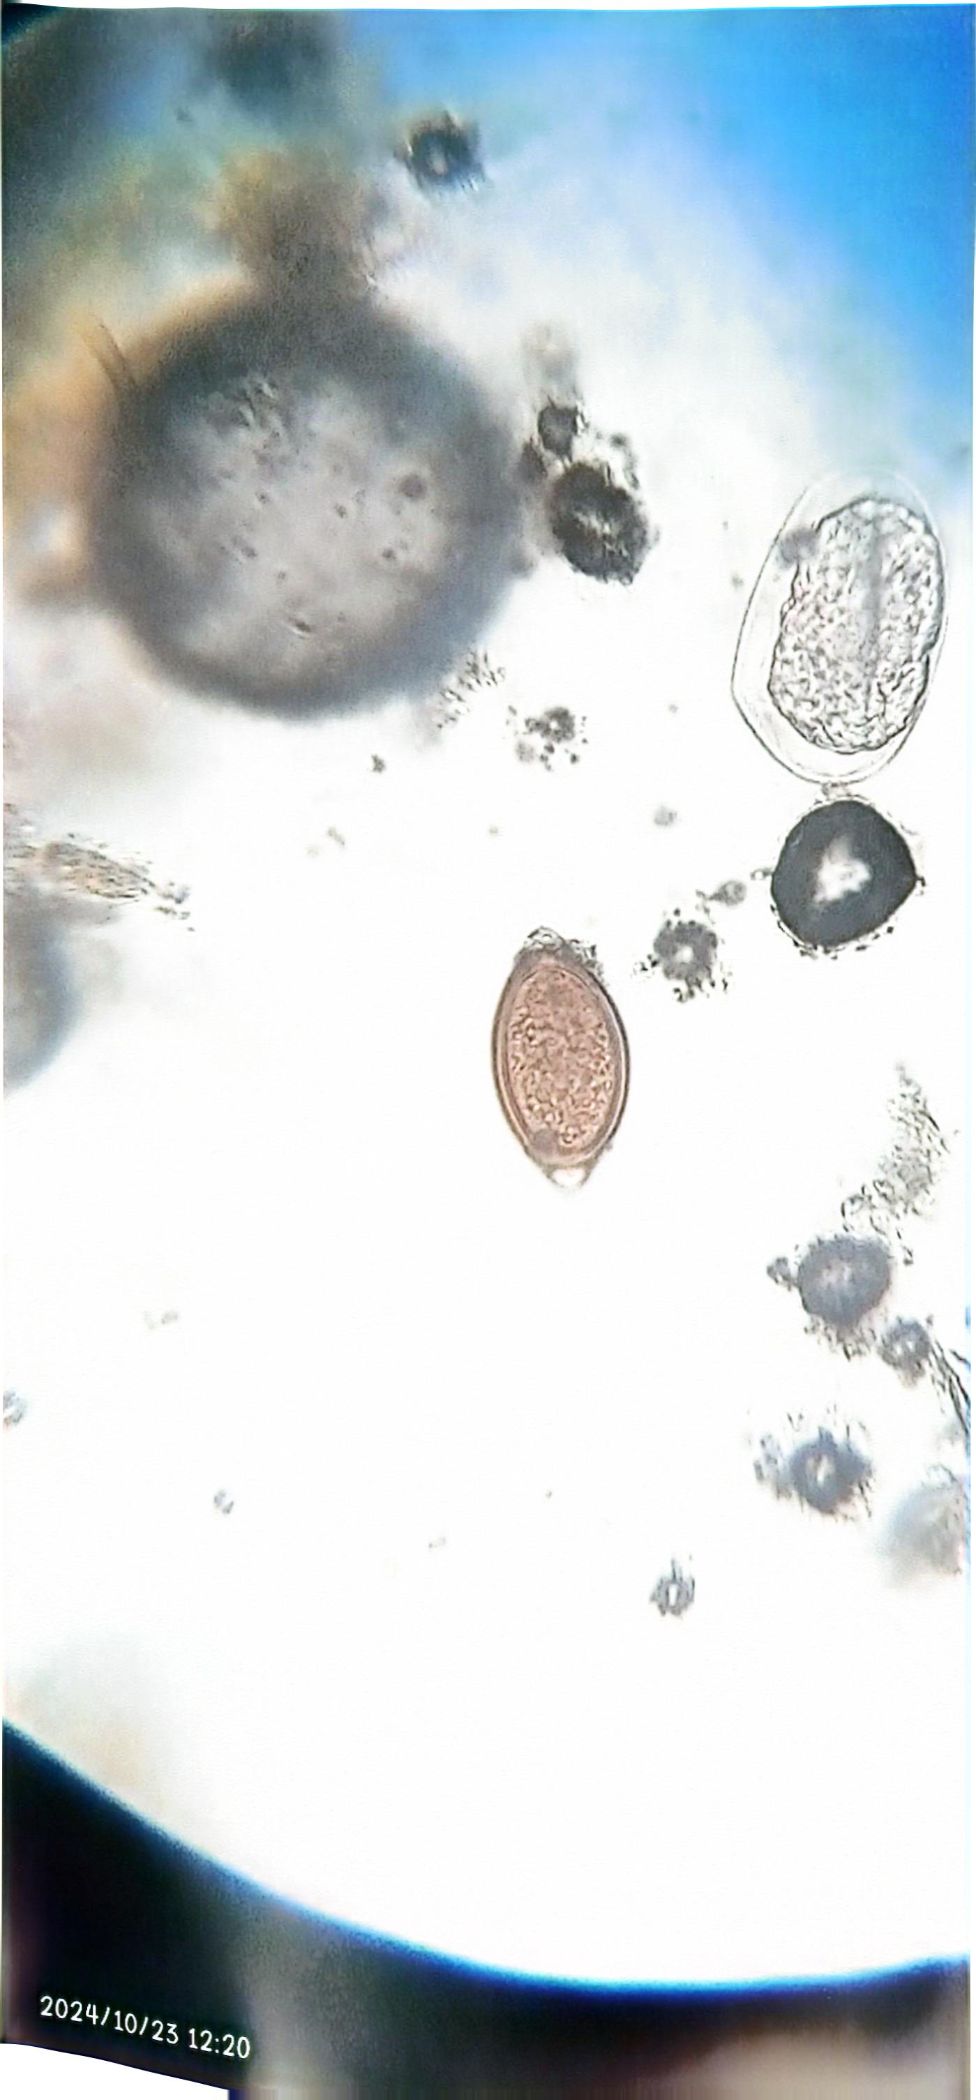

Prevalence of Gastrointestinal Parasite in Camel Slaughtered at the Maiduguri Central Abbatior, Borno State.